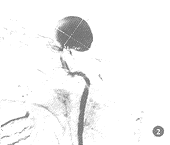

图2 图1病例DSA示颈内动脉C1段巨大动脉瘤,瘤腔内密度不均